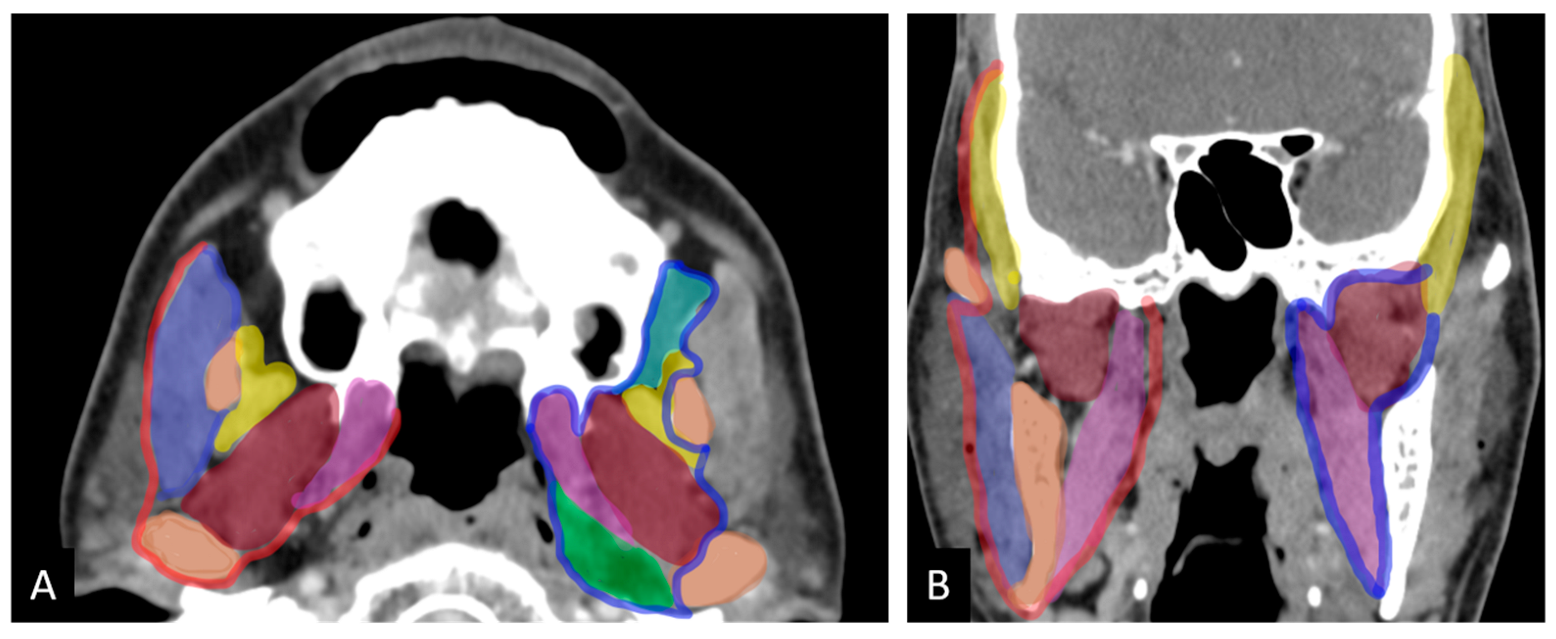

- Compartment 1: Low ITF (medial pterygoid)

- Compartment 2: Anterior high ITF (retroantral fat)

- Compartment 3: Posterior high ITF

- Compartment 3a: Paramandibular compartment (paramandibular fat/temporalis)

- Compartment 3b: Muscle compartment (lateral pterygoid)

- Compartment 3c: Perineural compartment (PPF/PMF).

- Compartment 1: Loss of fat planes with medial pterygoid.

- Compartment 2: Tumor extension into the high retroantral space, manifesting as mass or fat stranding.

- Compartment 3a: Loss of fat planes with temporalis muscle above the sigmoid notch or increased temporalis bulk with associated paramandibular soft tissue involvement.

- Compartment 3b: Loss of fat planes with lateral pterygoid muscle.

- Compartment 3c: Tumor extension into the pterygomaxillary fissure or pterygopalatine fossa.